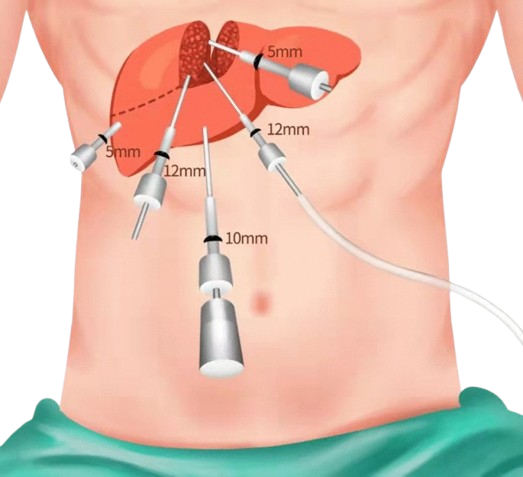

Laparoscopic liver surgery is a minimally invasive “keyhole” approach to removing benign or malignant liver tumors, cysts, or sections of the liver. Using specialized instruments and a camera through small abdominal…